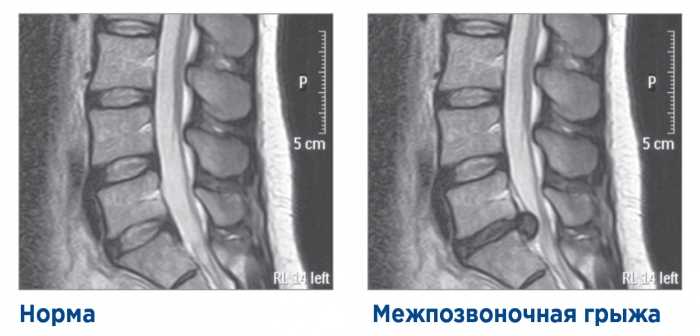

Сам момент образования грыжи ощущается больным как хруст или едва заметный щелчок в спине, после которого сразу появляется сильная боль. После возникновения такого рода ощущения необходимо незамедлительно вызвать скорую помощь или доставить пациента в клинику.

Для снятия приступа межпозвоночной грыжи рекомендуется соблюдать покой, избегать резких движений и поднятия тяжестей. Можно применять холодные компрессы на область боли для уменьшения воспаления, а также принимать нестероидные противовоспалительные препараты (по рекомендации врача). Легкие растяжки и физиотерапия могут помочь, но важно проконсультироваться с врачом для назначения индивидуального лечения.